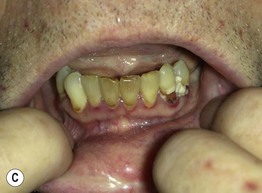

Fig. 43.6 Scurvy. A Corkscrew hairs and perifollicular hemorrhage on the lower extremities. B Hemorrhage beneath the buccal mucosa. C Gingival hypertrophy and infection, with loosened teeth. C, Courtesy, Jeffrey Callen, MD.

Fig. 43.7 Pellagra. A Hyperpigmentation with desquamation of the dorsal aspects of the hands and forearms. B Hyperpigmented desquamation of the distal lower extremity. Note the shiny shellac-like appearance on the lateral ankle.

Fig. 43.8 Zinc deficiency. Genetic (acrodermatitis enteropathica) (A–D) and acquired (E, F) forms. Both have erythema with erosions (A, E) as well as crusting (C, E, F) and desquamation (A, D–F). Lesions favor the acral and periorificial sites, and pustular paronychia may also be seen (B). Acrodermatitis enteropathica most often presents in infancy (A, B), but rarely, it is not diagnosed until later childhood, as in the case of this 11-year-old boy (C, D). A–D, courtesy, Julie V. Schaffer, MD.